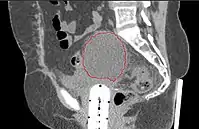

Lymphocele

- Seen postoperatively in up to 30% of GYN surgeries with pelvic/para-aortic LND

- Believed to arise from surgical transsection or inadequate ligation of draining lymphatics

- Lymphatic fluid may accumulate in various pelvic and retroperitoneal compartments

- Small lymphoceles typically resorb spontaneously

- Large lymphoceles may cause compression symptoms, and may result in abdominal distention, abdominal and pelvic pain, hydronephrosis, bladder dysfunction, constipation, tenesmus, edema of the ipsilateral leg and of the genitalia, and thromboembolism of iliac vessels

- Infection may cause fever, chills, and sepsis

- Symptomatic lymphoceles are typically managed initially with percutaneous CT-guided drainage, surgical therapy may be required

- Postoperative Lymphocele